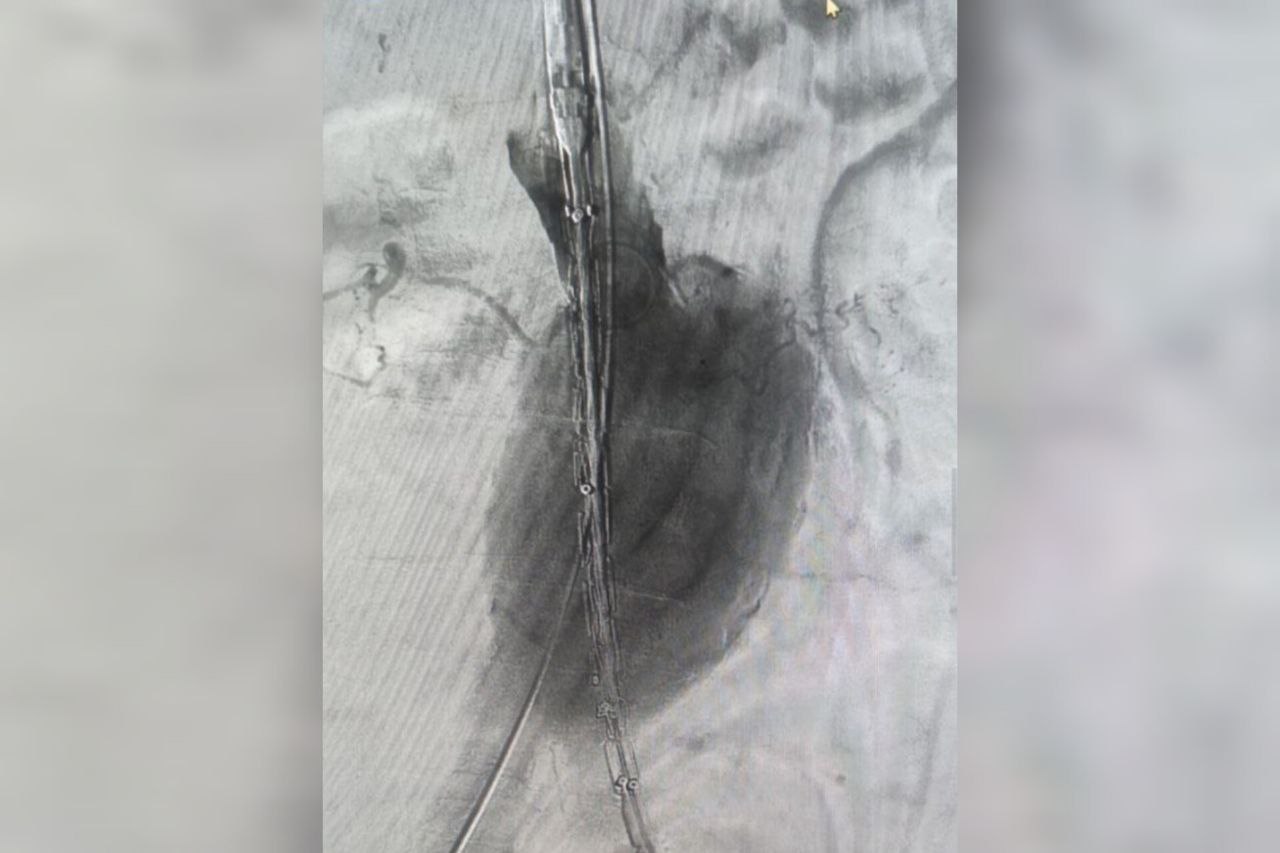

В Волгоградской областной больнице №1 провели уникальную операцию по установке стент-графта для лечения аневризмы брюшной аорты

Стент-графт укрепляет стенку аорты изнутри, создавая новый прочный канал для кровотока.